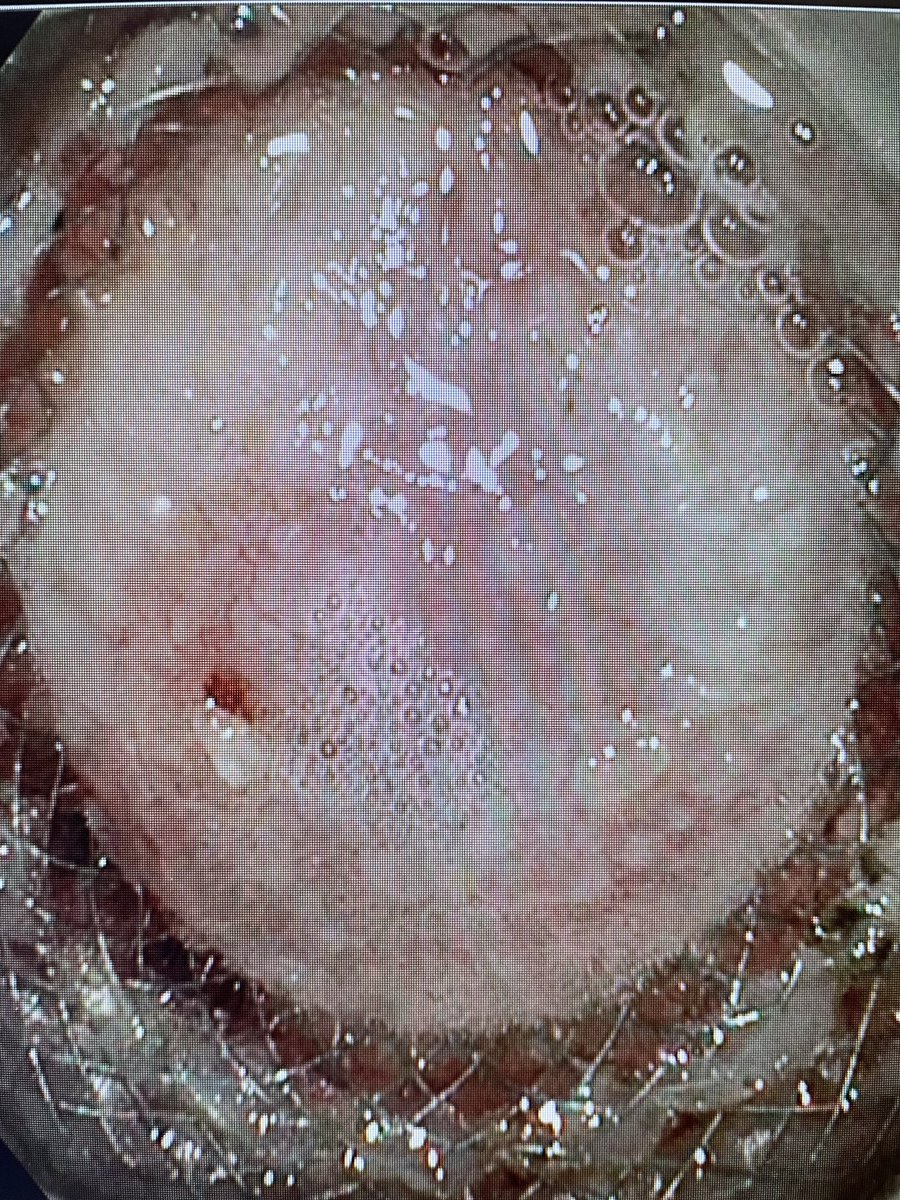

3/3 Endorotor + Basket = Cleared PFC! One session. Original cavity was 11cm. This was the first necrosectomy. #GITwitter ASGE GI Endoscopy GIE David Diehl Prof John Leeds

Now that is what I call resolved pancreatic necrosis! #gitwitter #surgery Prof John Leeds Neil Sharma, M.D. FASGE, FACG, AGAF Scot Michael Lewey

Emptiness never felt so good…..am I right? Douglas G. Adler MD, FASGE, FACG, AGAF Mankanwal Sachdev, MD FASGE Scot Michael Lewey Rizwan Jafri Joo Ha Hwang, MD PhD Edward Villa MD Samer El-Dika, MD Ali Mir Ahmed, MD Alex Schlachterman #endorotor #endoscopy

Just churning away at some thick pancreatic necrosis with the Endorotor... #surgery #gitwitter #medicine #pancreas #pancreatitis Scot Michael Lewey